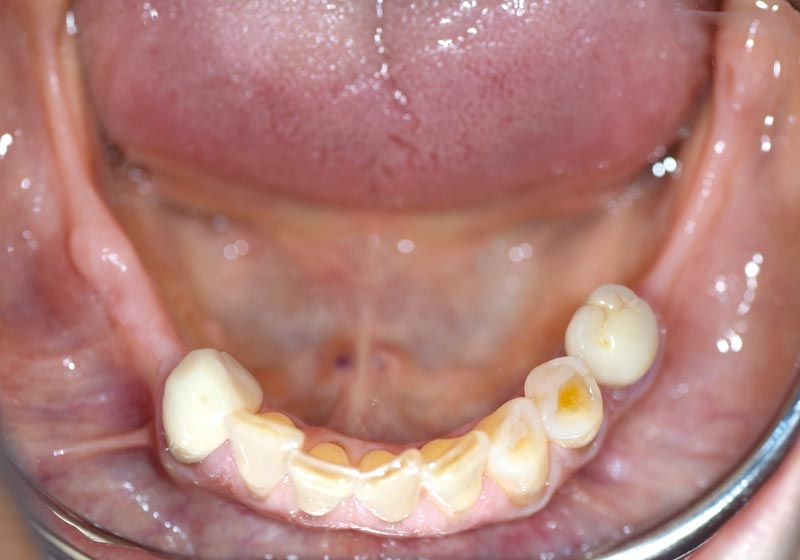

08/14 - Stable situation 5 months post augmentation

14/14 - Final clinical situation with prosthetics 18 months post augmentation